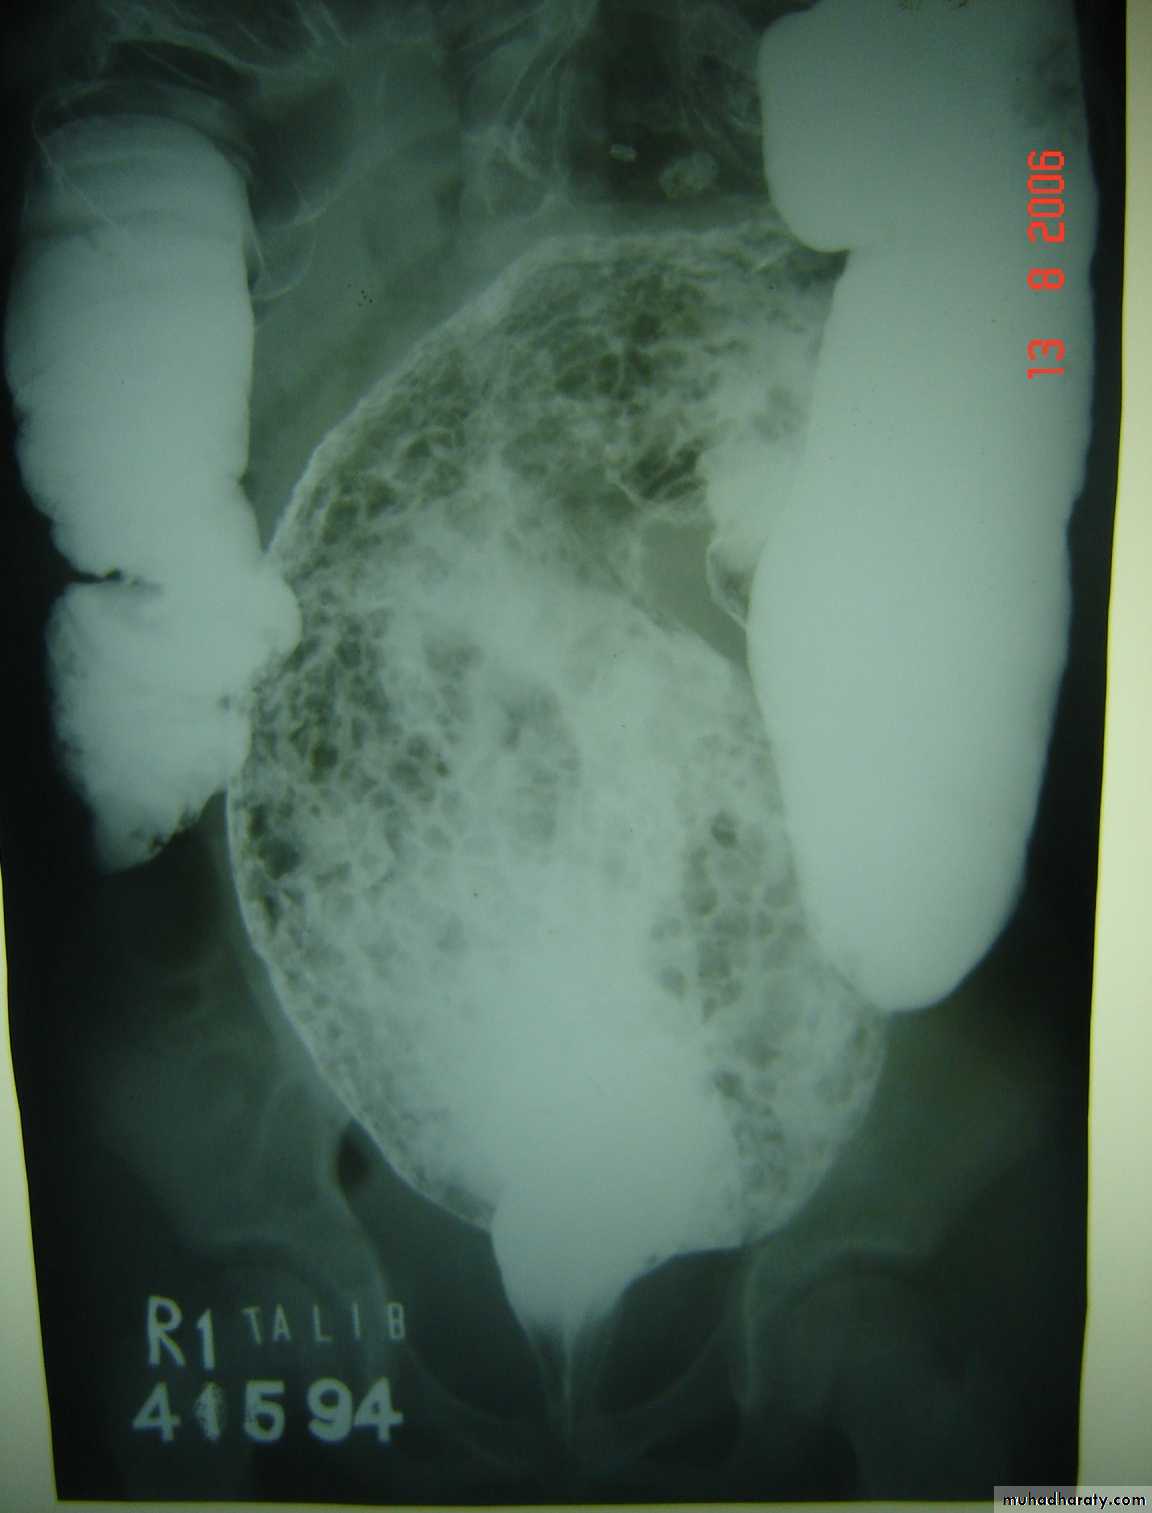

Hirschprungs disease

Description:

• Two years old child• Fist photo: Ba-enema test show dilatation of the sigmoid and narrowing of

• Recto-sigmoid junction and filled with material.

• The cause is problem in the ganglia

Presentation:

• Neonate delay to pass meconium – intestinal obstruction

• Old child chronic constipation – complications like enterocolitis (diarrhea)

and perforation

Treatment:

Surgery called pull-throughAbdominal Wall Defects